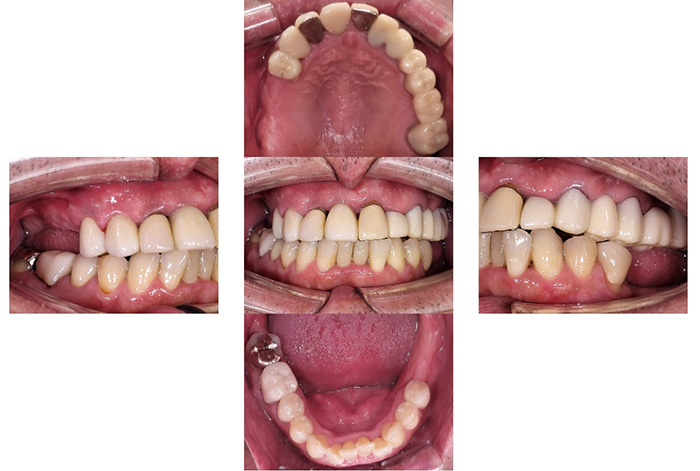

Before

After

前歯の見た目と噛み合わせのバランスを整えたケース

「前歯が強くかみ込んでいる気がする」「歯並びだけでなく、噛み合わせも気になる」

今回の患者様は、ディープバイト(過蓋咬合)による前歯の見た目と噛み合わせを気にされて来院されました。ディープバイトとは、上の前歯が下の前歯に深く重なっている噛み合わせのことで、見た目の問題だけでなく、前歯や顎への負担につながることがあります。

本症例では、マウスピース型矯正装置(インビザライン)を用いて治療を行いました。合計84枚のアライナーを使用し、歯並びだけでなく咬合の深さにも配慮しながら治療を進めました。

治療後は、前歯の見た目のバランスが整い、噛み合わせも改善しました。